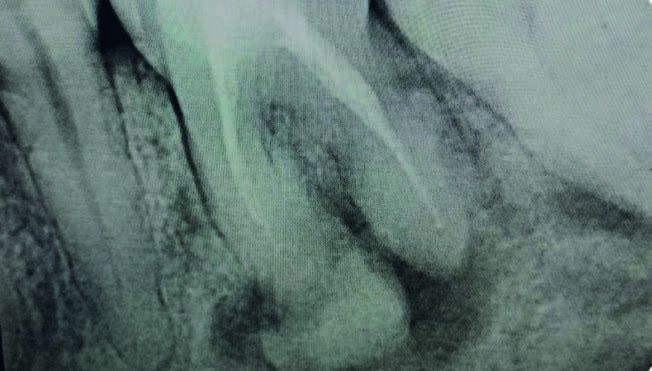

En noviembre de 2024, la paciente acudió a consulta presentando una fractura vertical en el molar 36, lo que requirió su exodoncia. A nivel radiográfico (Figura 4), se observó un aumento significativo de material radiodenso en la zona, particularmente en la región de la raíz mesial.

En el presente caso clínico, en 2018 se observaron lesiones proliferativas e inmaduras con una apariencia radiotransparente. En etapas más avanzadas de maduración, se identificaron masas radiodensas en las radiografías panorámica realizadas en 2021 y 2023. Estas masas hiperdensas, localizadas en las regiones de los dientes 36, 46, 47 y 43, estaban rodeadas por un área hipodensa y adheridas a las raíces de los dientes correspondientes. Las lesiones estaban bien delineadas del hueso circundante. Muchos autores han informado la presencia de un borde radiotransparente circundante característico y distintivo en la DCO13.